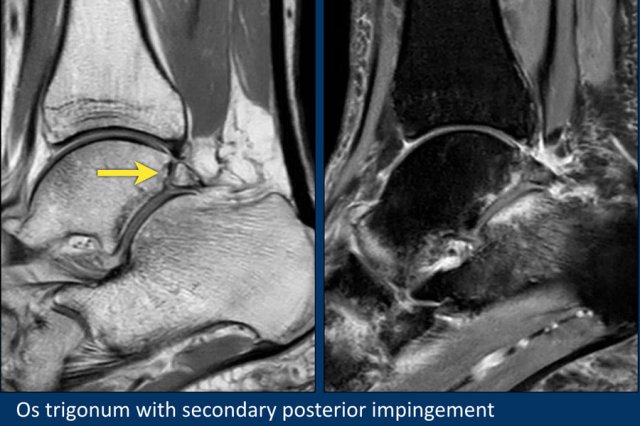

Os Trigonum

In the foot and ankle many accessory ossicles can be seen.

The most common ossicle is the os trigonum, which is a prominent unfused apophysis of the lateral tubercle of the talus.

The os trigonum is present in the normal population in about 5-15%.

Compression of the os trigonum and surrounding soft tissues between the tibia and the calcaneus during plantar flexion can be a cause of posterior impingement.

This is especially seen in ballet dancers.

Here another patient with an os trigonum.

On the fatsat images edema is present in the os trigonum and surrounding soft tissue.

This is an example of posterior impingement due to a symptomatic os trigonum.